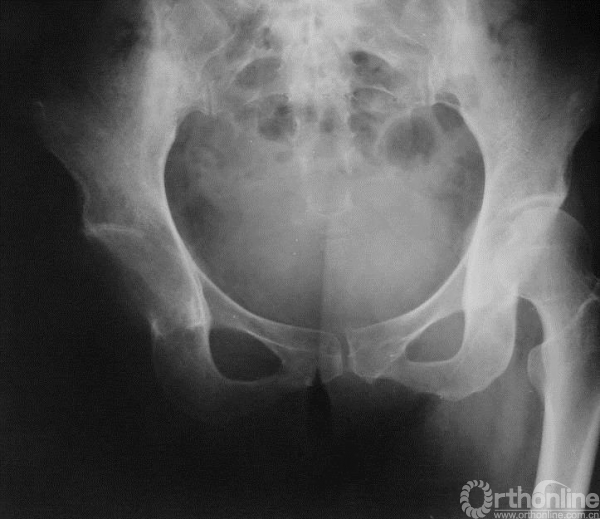

图15-11 第三次术后X线平片正位

髋关节离断术。

2. 对于骨肉瘤,由于既往两次手术暴露之处均可能有广泛的肿瘤污染,保肢手术风险极大;且肿瘤的上界接近股骨小粗隆,需行髋离断术才能达到安全的边界。另外,考虑到患者治疗过程较长,术前还应检查全身是否有转移病灶。

手术(第三次)